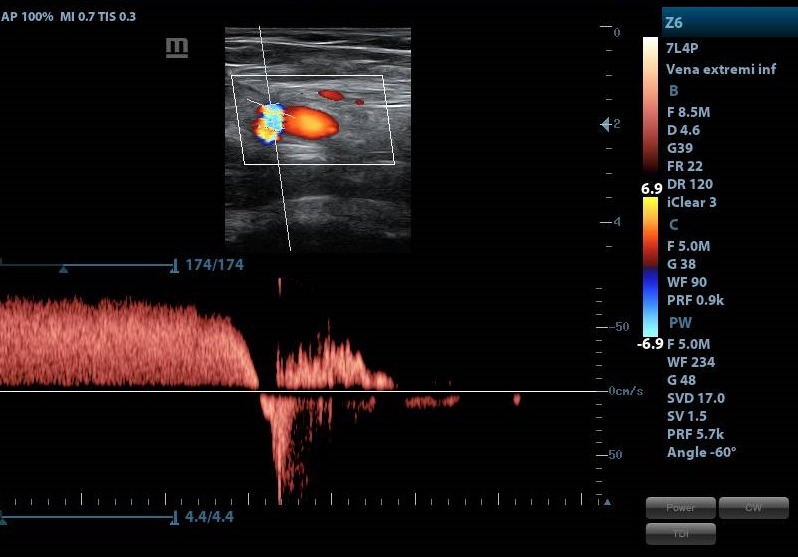

• Doppler venoso de miembros inferiores: Examina el flujo de sangre en las venas de las piernas. Su principal uso es detectar la trombosis venosa profunda (TVP), un coágulo de sangre que se forma en una vena profunda, y evaluar la insuficiencia venosa crónica, que provoca varices y úlceras. Este estudio complementa el Doppler arterial al enfocarse en el sistema de retorno de la sangre al corazón.